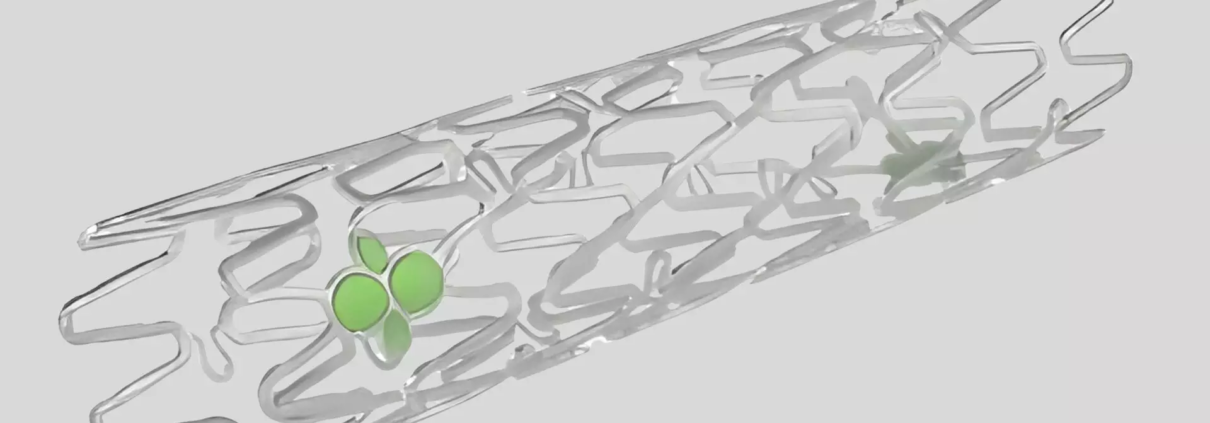

The IBS is a thin-strut (55–65 μm) bioresorbable scaffold made of Fe-0.05%N alloy as backbone material, coated abluminally with a PDLLA–sirolimus layer (8 μg/mm). It provides mechanical strength comparable to metallic stents and is designed to fully resorb over time, potentially reducing long-term risks such as late thrombosis or neoatherosclerosis.